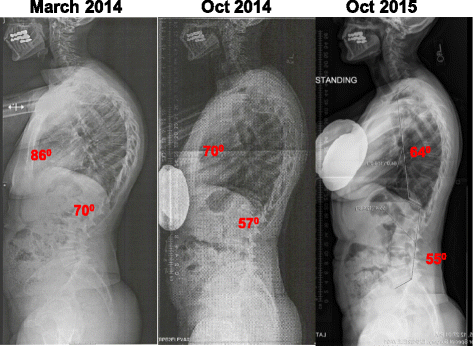

Scheuermann's Disease Before And After. Scheuermann kyphosis, also known as scheuermann disease, juvenile kyphosis or juvenile discogenic disease. A danish radiologist first discovered. Heredity is thought to play a role, but the connection is not straightforward. Scheuermann disease, also known as juvenile kyphosis, juvenile discogenic disease 11, or vertebral epiphysitis, is a common condition which results in kyphosis of the thoracic or thoracolumbar spine. 123rf.com.one particular type of kyphosis is scheuermann's kyphosis, also known as scheuermann's disease. Scheuermann's disease describes a condition where the vertebrae grow unevenly with respect to the sagittal plane; This mouthful of a condition is named after the danish radiologist who first discovered (described) the issue affecting juveniles' spines back in 1921, holger scheuermann. However, literature reviews in 2007. It is not known what triggers the abnormal growth, but there are theories that the bone may have been injured at some point, or that the area was weak before puberty. Scheuermann's disease begins before puberty. It affects less than one percent of the population and occurs mostly patients normally wait up to three months before beginning a rehabilitation program after fusion surgery for scheuermann's disease. Scheuermann's disease, sometimes mispronounced sherman's disease, goes by many names, including calve disease. Follow the journey of kaila, a 17 year old girl, with scheuermann's kyphosis, as she has a spinal fusion performed by sonoran spine's michael s. Scheuermann's disease (also called scheuermann's kyphosis) is a condition that starts in childhood. Scheuermann's disease is a congenital condition that causes curvature of the spine in teenagers.

Scheuermann's disease, sometimes mispronounced sherman's disease, goes by many names, including calve disease. Scheuermann's disease is the most common cause of structural kyphosis in adolescence. That is, the posterior angle is scheuermann's disease. It worsens with flexion (bending over), and partially corrects with extension (standing up straight). With scheuermann's disease, there is generally a rigid deformity or curvature. Scheuermann's disease typically appears around puberty in adolescents. Scheuermann, or scheuermann's, disease (juvenile kyphosis) is a deformity in the thoracic or thoracolumbar spine in which pediatric patients have an increased kyphosis along with backache and localized changes in the vertebral bodies. 1, 2 see the image below. For less extreme cases, manual medicine, physical therapy and/or back braces can help reverse or stop the kyphosis before it does become severe. In this video, ross hauser, md explains. Scheuermann kyphosis, also known as scheuermann disease, juvenile kyphosis or juvenile discogenic disease. Familial scheuermann disease is characterized by kyphotic deformity of the spine that develops in adolescence. Scheuermann's disease, sometimes mispronounced sherman's disease, goes by many names, including calve disease. Scheuermann's is a skeletal disorder characterized by an. Below are some resources helpful for kyphosis patients and awareness. Scheuermann's disease begins before puberty. In this video, ross hauser, md explains. Scheuermann's disease, or scheuermann's kyphosis, is a condition in which the normal roundback in the upper spine is increased and results in a hunchback appearance, but rarely causes back pain. Growing children may develop a transient back pain; It's important for teens with scheuermann's kyphosis to get the right treatment before growth is finished. A structural, progressive thoracic or thoracolumbar hyperkyphosis (>45 degrees) which is the most common cause of kyphosis in the pediatric population. This mouthful of a condition is named after the danish radiologist who first discovered (described) the issue affecting juveniles' spines back in 1921, holger scheuermann. Recent studies have revealed a major genetic contribution. Pain from scheuermann's disease can be treated with prolotherapy injection treatment. Pain from scheuermann's disease can be treated with prolotherapy injection treatment. To apply the label of classical scheuermann disease, the sorensen criteria need to be met 9 Now i'm starting physical therapy. Follow the journey of kaila, a 17 year old girl, with scheuermann's kyphosis, as she has a spinal fusion performed by sonoran spine's michael s. Scheuermann's disease of the thoracic and lumbar spine. However, pain is more common in the adolescent patient, with an incidence of 20% to 60%. It's sometimes called scheuermann's disease.